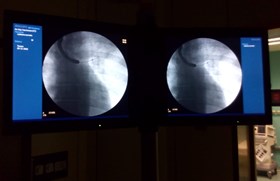

Cancro al pomone, diagnosi con mini-sonde

Innovativa metodica "mini probe" in Chirurgia Toracica